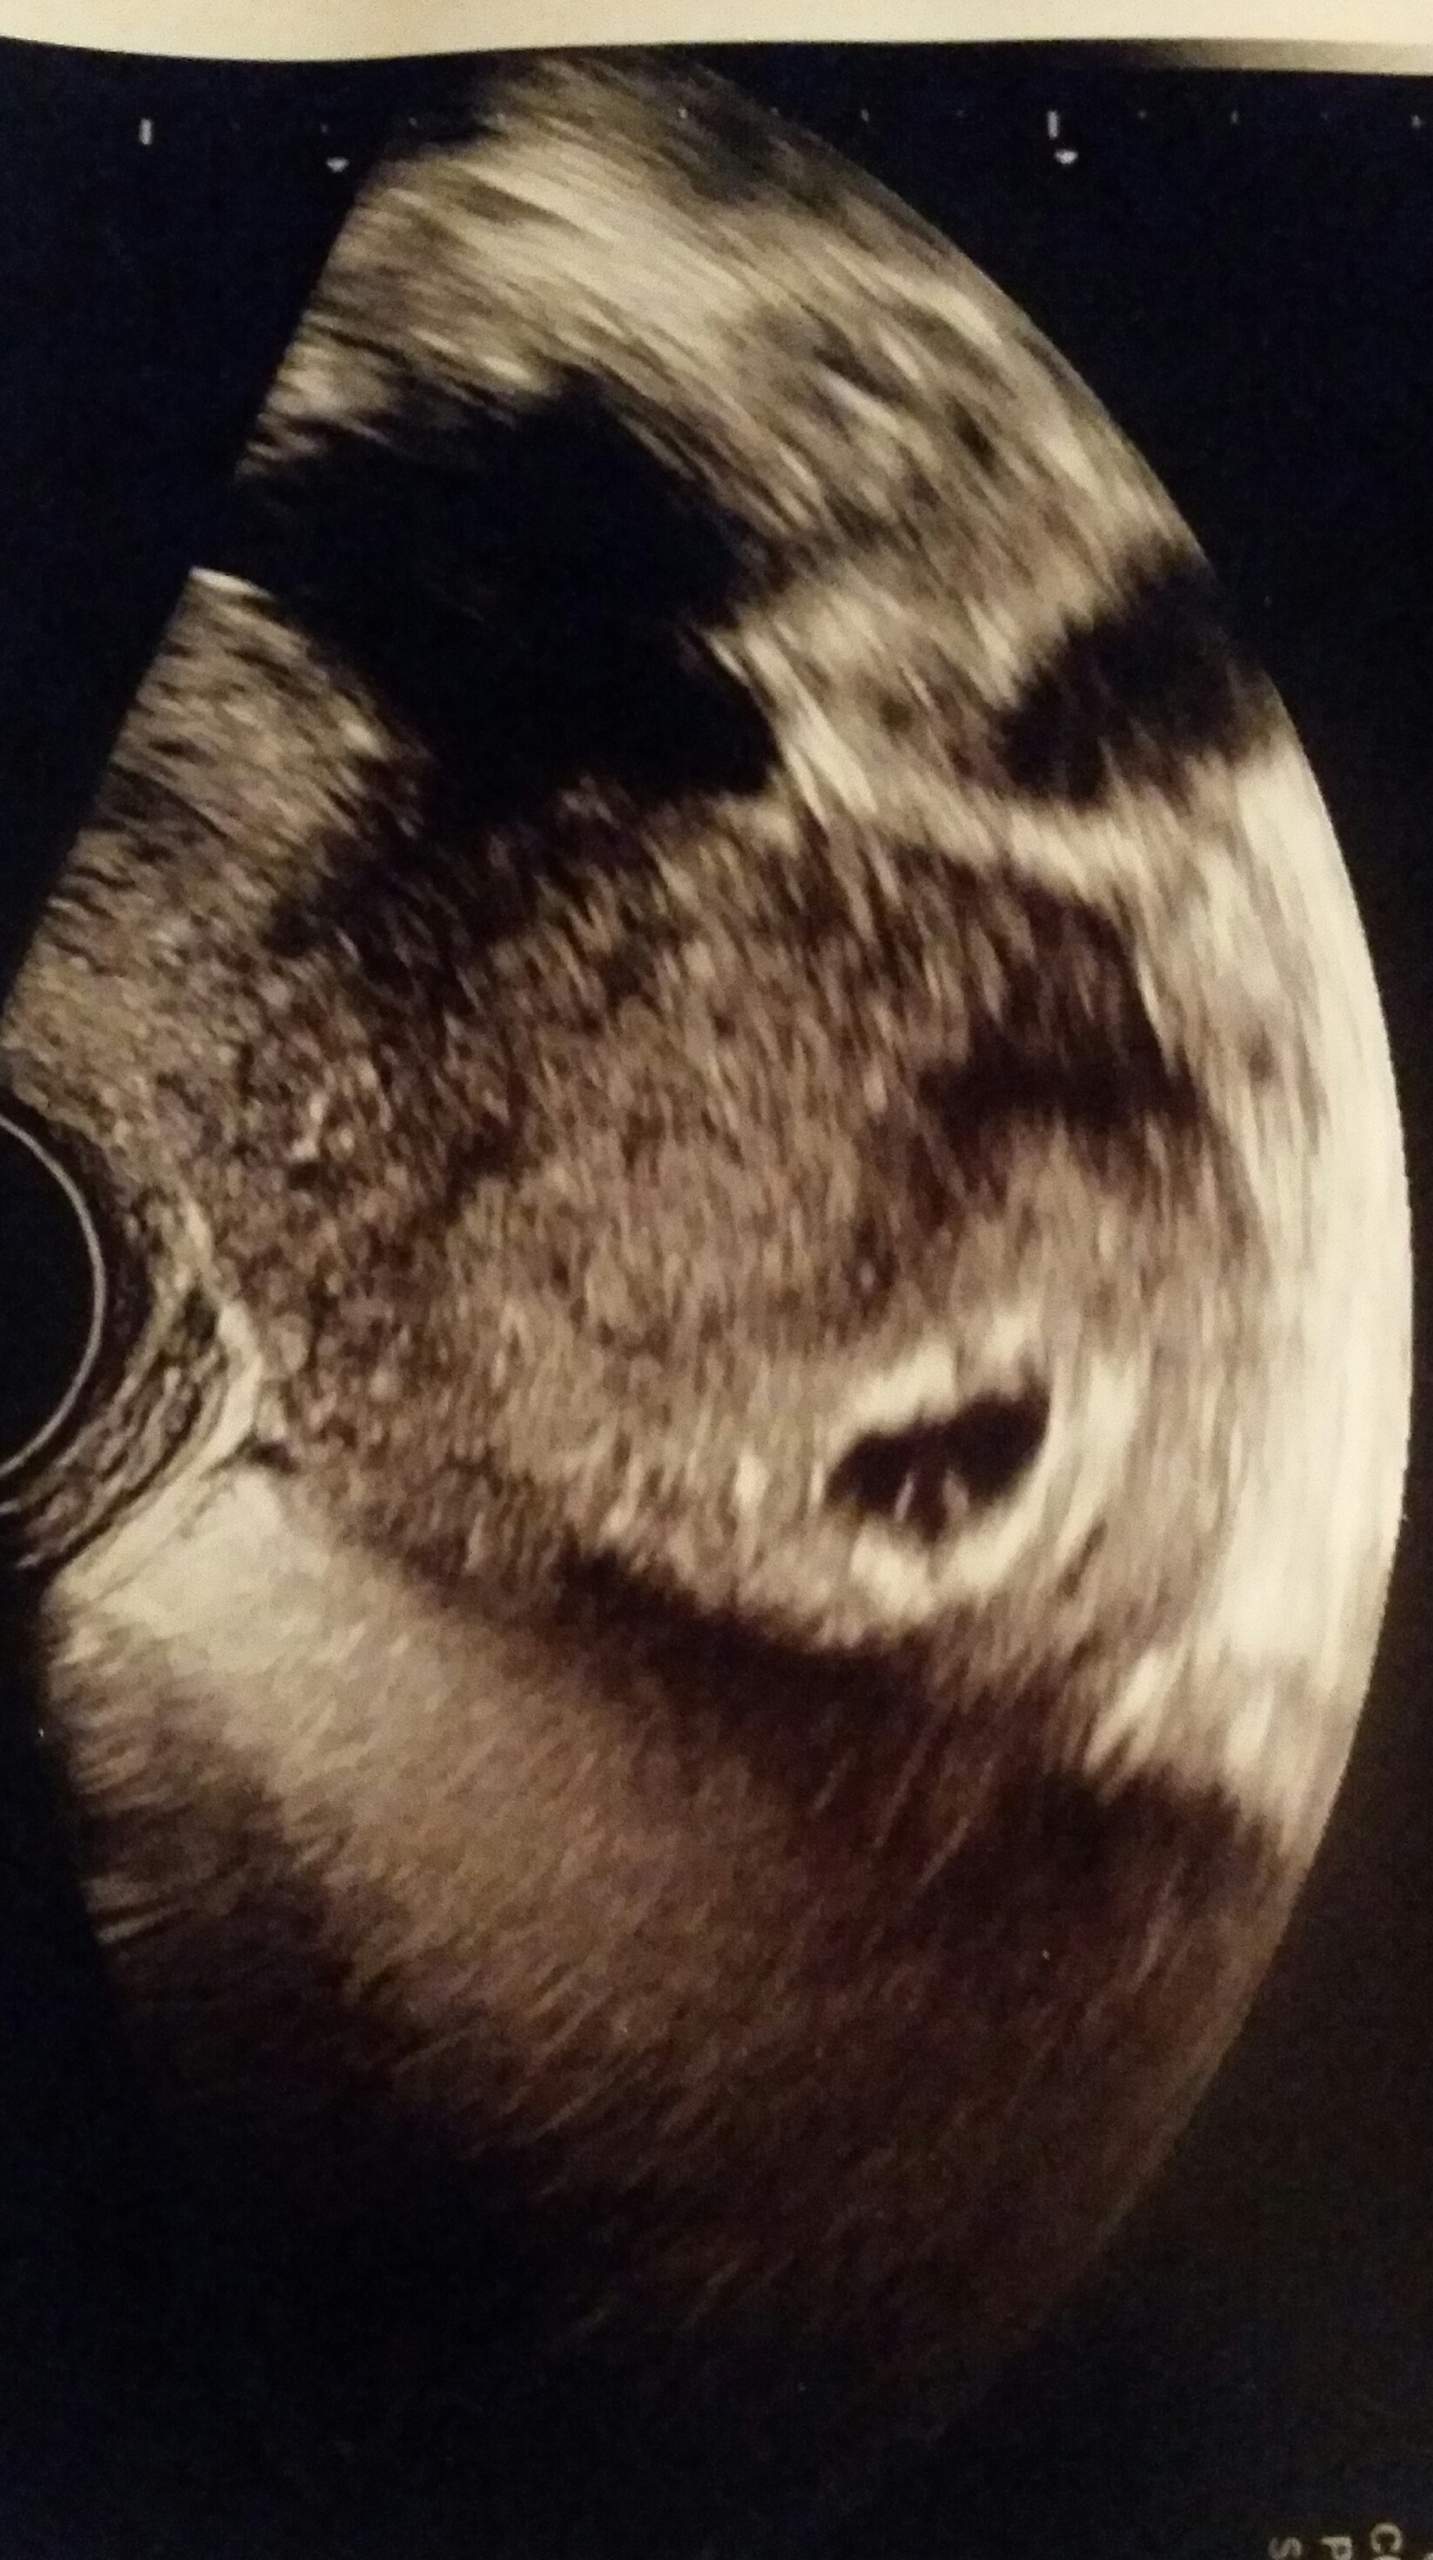

Als ich in der 7 Woche war sah man die Fruchthöhle den Dottersack und den Embryo. Es kommt öfters vor dass um die 6SSW nur eine leere Fruchthöhle zu sehen ist. Sie vermuten eine Eileiterschwangerschaft.

Bei meiner tochter hat man bereits in der 61 ssw einen kleinen dottersack und ein embryo sehen können. Dottersack aber kein Embryo.